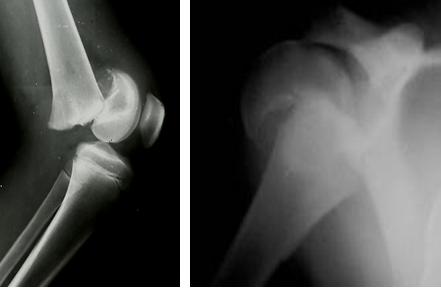

Si tratta di lesioni che si osservano nei bambini prima della saldatura della cartilagine di coniugazione e in cui la linea di separazione passa attraverso la cartilagine epifisaria per tutto il suo percorso o parte di esso. In questo secondo caso si associa una frattura dell’epifisi cartilaginea o di un nucleo epifisario oppure della metafisi.

I distacchi epifisari vengono classificati in puri e misti a seconda che vi sia coinvolgimento anche della metafisi o del nucleo epifisario. La classificazione più utilizzata nella pratica clinica quotidiana è quella di Salter-Harris che suddivide i distacchi in 5 tipi.

- Tipo 1: puro completo – in genere la consolidazione è rapida e non vi sono disturbi di accrescimento

- Tipo 2: più frequente in assoluto – oltre alla fisi è interessata obliquamente la metafisi – in genere la prognosi è buona

- Tipo 3: raro - interessa longitudinalmente la cartilagine di accrescimento e obliquamente l’epifisi – prognosi discreta

- Tipo 4: Interessata longitudinalmente la cartilagine di accrescimento e la metafisi coinvolgendo il nucleo epifisario ed interrompendo il periostio- prognosi più incerta

- Tipo 5: schiacciamento dello strato basale della cartilagine di accrescimento con scarso spostamento (spesso diagnosi difficile ed errata) - Prognosi cattiva.

Talvolta una precisa classificazione radiografica (specie in caso di scarso spostamento o in distacchi complessi) è complessa e si rende necessario un approfondimento diagnostico con RM.